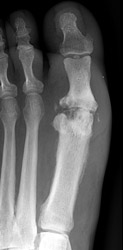

1. Distribution:

The joint contamination may be monarticular or polyarticular. Weight bearing

joints are commonly involved.

2. Erosion pattern: Soft tissue swelling and joint effusion may comprise early findings. As the infection progresses, poorly defined bony destruction with indistinct superficial marginal erosions may be evident along the articular surfaces. This may be accompanied by joint space narrowing, secondary to chondral destruction. Joint space ankylosis may occasionally occur in advanced cases.